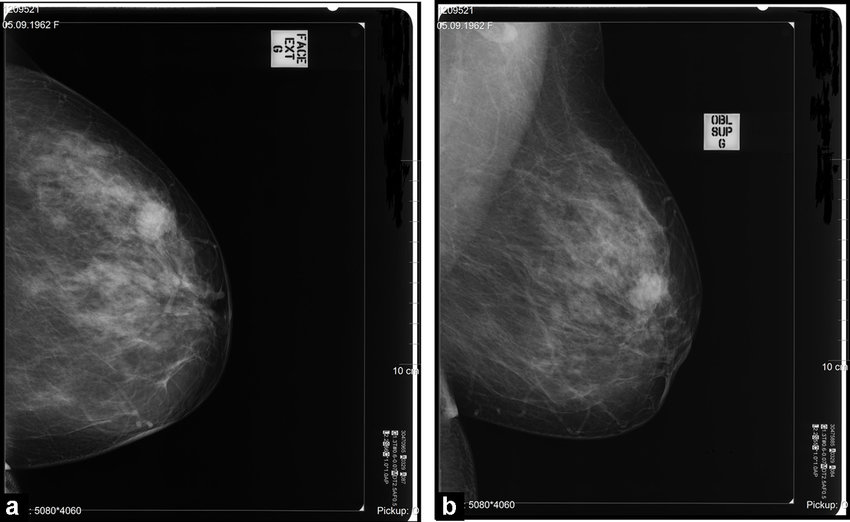

A partir de los 40 años, todas las mujeres deben realizarse mamografías anuales. Aunque las mamografías no previenen el cáncer, pueden detectar la enfermedad temprano, lo que puede aumentar sus posibilidades de supervivencia y brindarle más opciones de tratamiento. El cáncer de mama detectado temprano, cuando todavía está localizado en la mama, tiene una tasa de supervivencia de hasta el 99%.

Nuestros proveedores utilizan mamografías 3D de vanguardia para producir imágenes más claras del tejido mamario desde múltiples ángulos, y ofrecemos exámenes de ultrasonido mamarios automatizados para mujeres con mamas densas. Estas tecnologías permiten a nuestros radiólogos detectar anomalías con mayor facilidad y, lo que es más importante, potencialmente salvarle la vida.